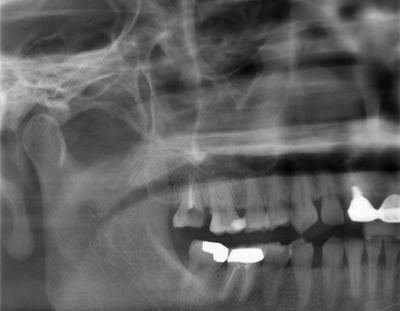

术前X-ray

术前X-ray局部放大图